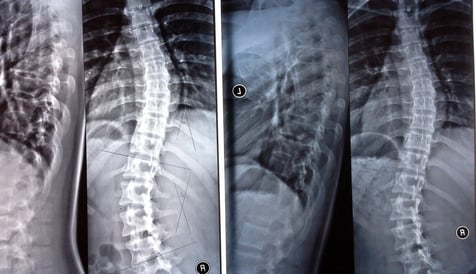

★改善例7 18歳女の子

側弯のカーブがきつめの子でした。

背中がときどき痛むとのことでした。

カイロプラクティックケアを開始して、6か月後に再度レントゲンをとりました。

上のカーブは45度から39度へ、下のカーブは46度から40度へ減少しました。

本人も身体が軽くなった、背中の痛みが減ったとのこと。また、自分の背中の曲がりに対して、コンプレックスが少なくなったとおっしゃいました。